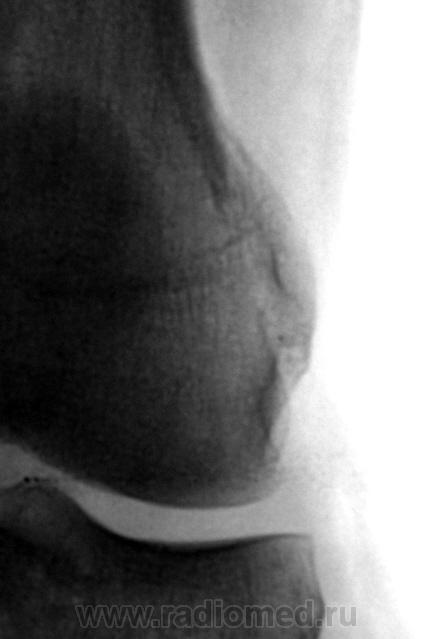

Травма.  Пациент направлен на рентгенографию коленного сустава.